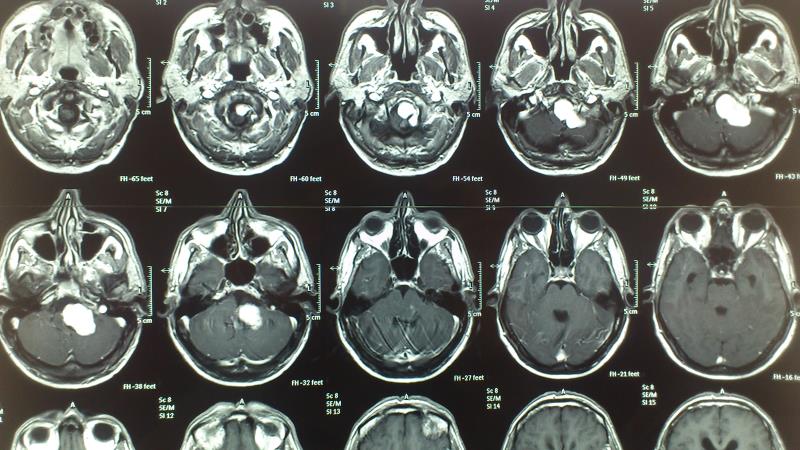

Ασθενής  άνδρας 55 ετών  προσήλθε λόγω αστάθειας βάδισης  και πάρεσης  των κατώτερων εγκεφαλικών συζυγιών  ( ΙΧ,Χ,ΧΙ ). Ο  έλεγχος με μαγνητική τομογραφία εγκεφάλου ανέδειξε εικόνα συμβατή  με μηνιγγίωμα ινιακού τρήματος με σημαντική πίεση επί του στελέχους. Ο ασθενής υποβλήθηκε σε αριστερή  Far Lateral Transcondylar προσπέλαση. Μετεγχειρητικά ο ασθενής παρουσίασε ήπια επιδείνωση της πάρεσης των κατώτερων εγκεφαλικών συζυγιών που ωστόσο αποκαταστάθηκε σταδιακά στα προεγχειρητικά επίπεδα Ο μετεγχειρητικός απεικονιστικός έλεγχος ανέδειξε ολική αφαίρεση του όγκου.

Μετεγχειρητικός απεικονιστικός έλεγχος